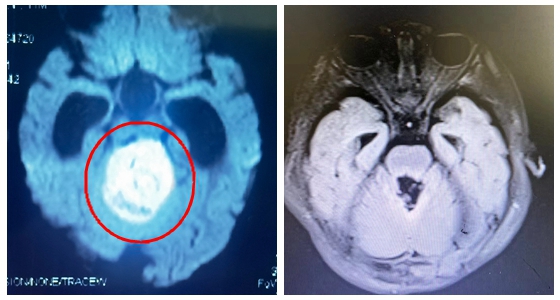

众所周知,脑干是人的生命中枢,曾经一度被认为是手术“禁区”,而脑干肿瘤甚至在一定程度上被认为是无法救治的。近日,湘雅常德医院神经外科勇闯“禁区”,成功为一例11月龄的婴儿完成脑干...